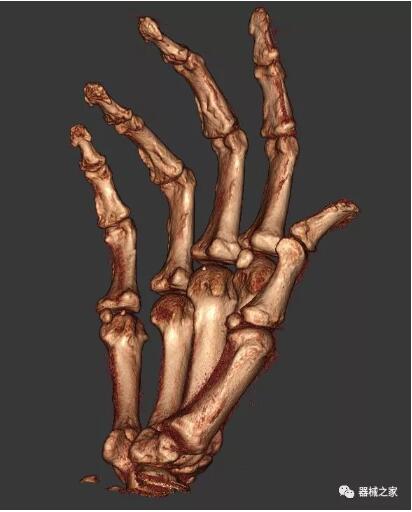

以下是這些“特立獨行”的CT所拍出來的圖像: